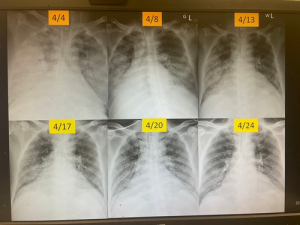

一位五十二歲男性病人,上呼吸道症狀到診所就醫,病情惡化後轉花蓮慈院急診檢查,胸部X光片發現右半邊肺葉全部白掉,花蓮慈濟醫院風濕免疫科主任蘇桂英指出,病人到院血壓明顯偏低,一度休克失去意識,幸在內科加護病房醫治時,主治醫師莊立良在第一時間聯想到檢驗自體免疫疾病,讓病人及早正確治療。